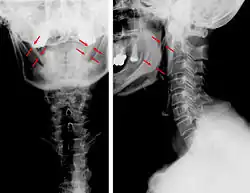

| Anteroposterior and lateral radiographs of cervical spine showing ossification of the stylohyoid ligament on both sides | |

Radiograph, lateral view showing elongated stylohyoid process and stylohyoid ligament ossification -

Radiograph, lateral view showing joint-like formation in ossified stylohyoid ligament -